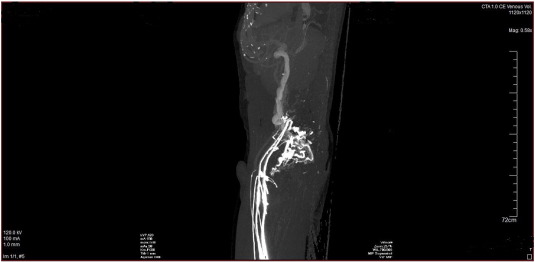

Fig. 1 ;  Fig. 2 are the CT angiography images of the venous system of the lower extremities and inferior vena cava of a 44 year old Caucasian male who presented with a long history of intermittent edema of both lower extremities. His clinical examination was perfectly normal. CT angiography of the lower extremities and IVC demonstrated patent popliteal, femoral and iliac veins with a completely absent IVC. Massively dilated collateral vessels were visible with large, dilated azygos and hemi-azygos veins. The azygos vein drained into the superior vena cava. In addition the lumbar veins were dilated with multiple collaterals present in the pelvis and abdomen. He tested heterozygous for the factor V Leiden mutation (R506Q).

CT angiography image demonstrating absence of the infra- and suprarenal portions ...

Fig. 2.

CT angiography image demonstrating absence of the infra- and suprarenal portions of the inferior vena cava with numerous collateral vessels from a lateral view.